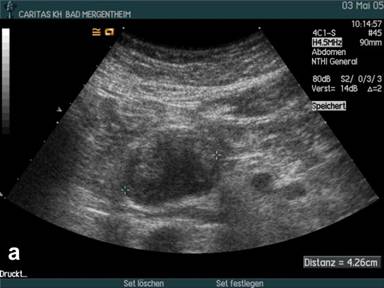

Mucinous Cystadenoma

During the study period we examined 11 patients by CEUS with mucinous neoplasia (all except one lesion located in the corpus or tail of the pancreas; 2 benign, 9 malignant; all operated). The mean diameter of the lesions was 61±18 mm (range: 40-83 mm). Using conventional B-mode mostly peripherally located solid nodules were displayed in 9 out of 11 patients (81.8%). Contrast enhancement was found in all 9 nodules (Figure 3). Isolated macrovessels transversing the cyst(s) could not be visualised.

Figure 3. B-mode imaging (a.) and contrast enhanced ultrasound (CEUS) (b.) in a patient with mucinous cystadenoma displaying the mainly cystic but partially also solid tumour. |